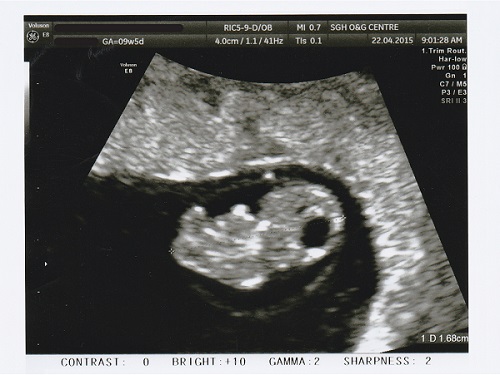

*Throwback post to week 8*

It was rather exciting to see you for the first time. I still can’t believe it that you’re alive and inside of me. It was an incredible moment for your daddy and me to see your little heart beating. All my worries for the past few weeks are gone, knowing now that you are alright.

My little jellybean says hi.

PS: It is a miracle of life. At week 8, my baby is hardly 2cm but its little heart is already beating.